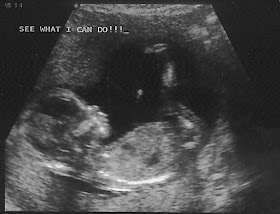

3d Ultrasound Baton Rouge La

First Glimpse 3d 4d Ultrasound Of Baton Rouge 8312 Jefferson Hwy

First Glimpse 3d 4d Ultrasound Of Baton Rouge 24 Photos 15